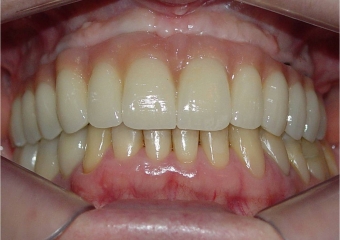

Prótese fixa superior em porcelana

Sorriso final, do caso terminado em fevereiro de 2014